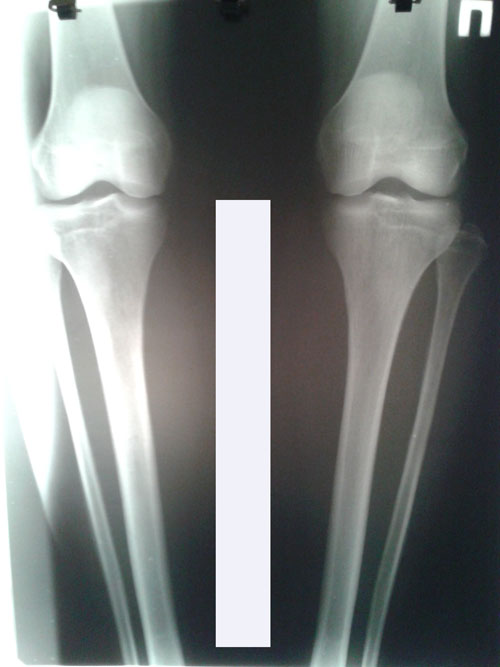

Исходник.

38 лет.

РЕНТГЕН ДО ОПЕРАЦИИ